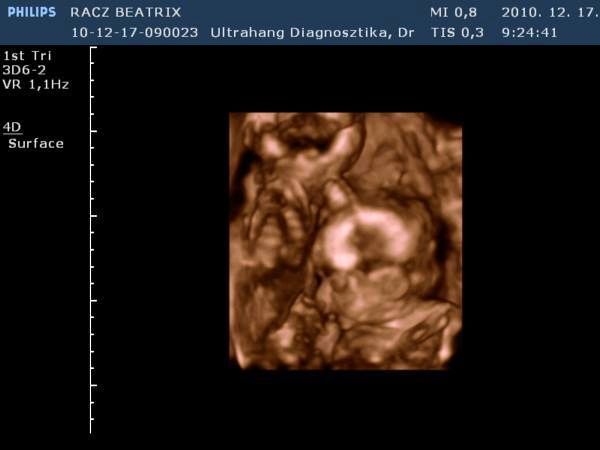

Gyorsan növöget az egyszemkénk, remélem lassan megtudjuk a nemét is! Afp-re dec. 27-én megyek. Az "A" baba még mindig ott van a hegemen és már úgy néz ki ott is marad, majd elnyomja a "B" baba mikor már nagyobb lesz kb a 18-20. héten. De van olyan is akinek szülést követően a méhlepényén találják meg mint egy freskót rajta. Teljesen ott lesz a lenyomata. Majd meglátjuk mi lesz...